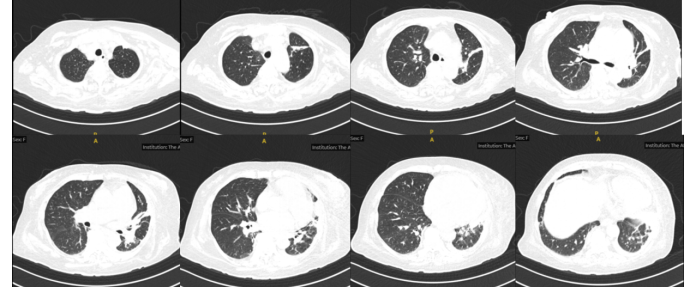

1)感染性休克:患者反复发热,炎症指标明显升高,胸部CT提示两肺感染,SOFA评分>2分,伴血压下降。感染诱发病情加重可能性较大,迅速调整治疗方案,予比阿培南抗感染治疗,2天复查炎症指标白细胞降至19.8×109/L,中性粒细胞19.16×109/LCRP 77.4 mg/L,PCT 13.8 ng/ml。复查胸部CT发现,患者肺部感染程度不能解释其感染性休克的表现3,考虑可能合并其他部位的感染。患者结合胆红素140 U/L(占总胆红素的60%以上)明显升高考虑为梗阻性黄疸可能性大,及时完善腹部CT和彩超,报告:脾大,胰腺尾部密度不均匀,胆囊壁水肿、增厚,胆囊腔密度增高,管扩张4考虑胆囊炎并胆管炎继发感染性休克可能。2天加用替加环素50 mg q12h。

3  患者转入RICU后复查胸部CT

4   患者转入RICU后腹部CT